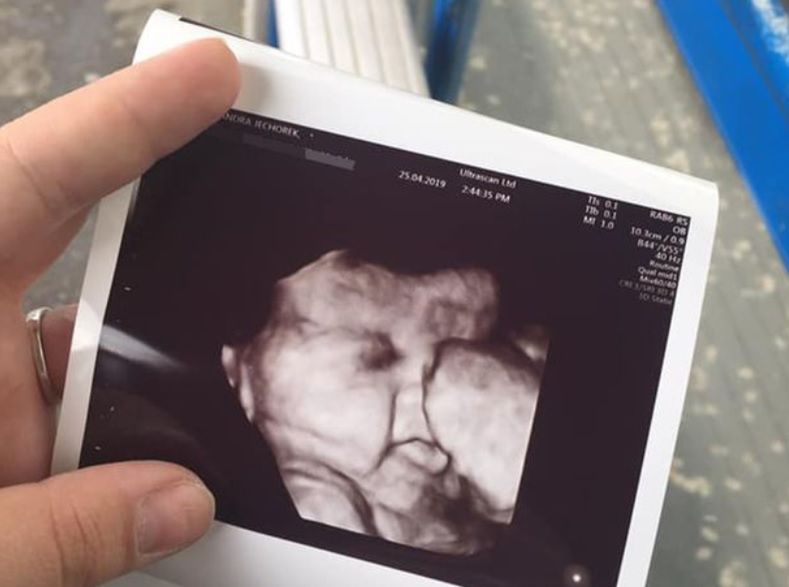

Mama dziewczynki opowiadała, że już podczas badań USG, wykonywanych pod koniec ciąży, było widać, że ich dziecko będzie miało bujne włosy. Początkowo nie mogła w to uwierzyć.

"Dowiedzieliśmy się, że spodziewamy się dziewczynki na poprzednim badaniu, więc po 34 tygodniu byliśmy podekscytowani, widząc, jak bardzo urosła. Kiedy położna odwróciła ekran, szczerze mówiąc, nie mogłam uwierzyć. Na skanie było małe maleństwo z gęstymi włosami. Po prostu pomyślałam: nie ma mowy, to niemożliwe" – opowiadała mama dziewczynki w rozmowie z Daily Star.